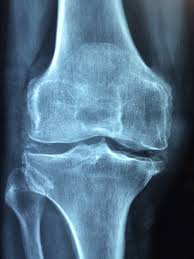

무릎은 우리 몸에서 체중을 지탱하는 가장 큰 관절 중 하나로, 다양한 이유로 시큰거리는 통증이 발생할 수 있습니다. 특히 나이가 들면서 연골이 닳거나, 과도한 운동, 외상, 잘못된 생활습관 등이 원인이 될 수 있습니다.

무릎 시큰거림은 단순한 피로가 아니라 관절염, 연골 손상, 인대 질환의 신호일 수 있어 주의해야 합니다. 오늘은 무릎이 시큰거리는 원인과 대처법을 구체적으로 알아보겠습니다. 아래에 글 전체를 요약해 놓았으니 꼭 끝까지 읽어보세요!

1) 퇴행성 관절염

노화로 인해 연골이 닳아 없어지면 무릎이 시큰거리는 통증이 발생합니다. 퇴행성 관절염은 50대 이상에서 흔히 나타납니다. 만성적이고 점진적인 악화가 특징입니다. 조기 관리가 진행을 늦출 수 있습니다. 정기 검진이 필요합니다.